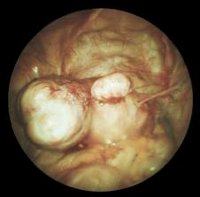

Подсерозная фиброма матки

Подсерозная (субсерозная, подбрюшинная) фиброма развивается на наружной поверхности матки в области брюшины, иногда вырастает на других фиброидных узлах. Ввиду наружного роста подсерозного узла матка приобретает узловатую бугристую форму. Подсерозная фиброма матки может иметь широкое основание либо вытянутую ножку (педункулярная фиброма). При подсерозном варианте узел фибромы иногда располагается отдаленно от матки, в области ее связок. В случае перекрута педункулярной фибромы развивается отек фиброидного узла и его некроз.

При гинекологическом осмотре на кресле обращают внимание на неравномерное увеличение размеров матки, ее бугристую поверхность. Для подтверждения диагноза подсерозной фибромы матки выполняется трансабдоминальное или трансвагинальное УЗИ, с помощью которого уточняются локализация, характер роста, размеры и форма опухолевого узла. При трудностях в различении подсерозной фибромы матки и кистомы яичника может потребоваться проведение томографических (КТ малого таза, ЯМР) исследований или диагностической лапароскопии.